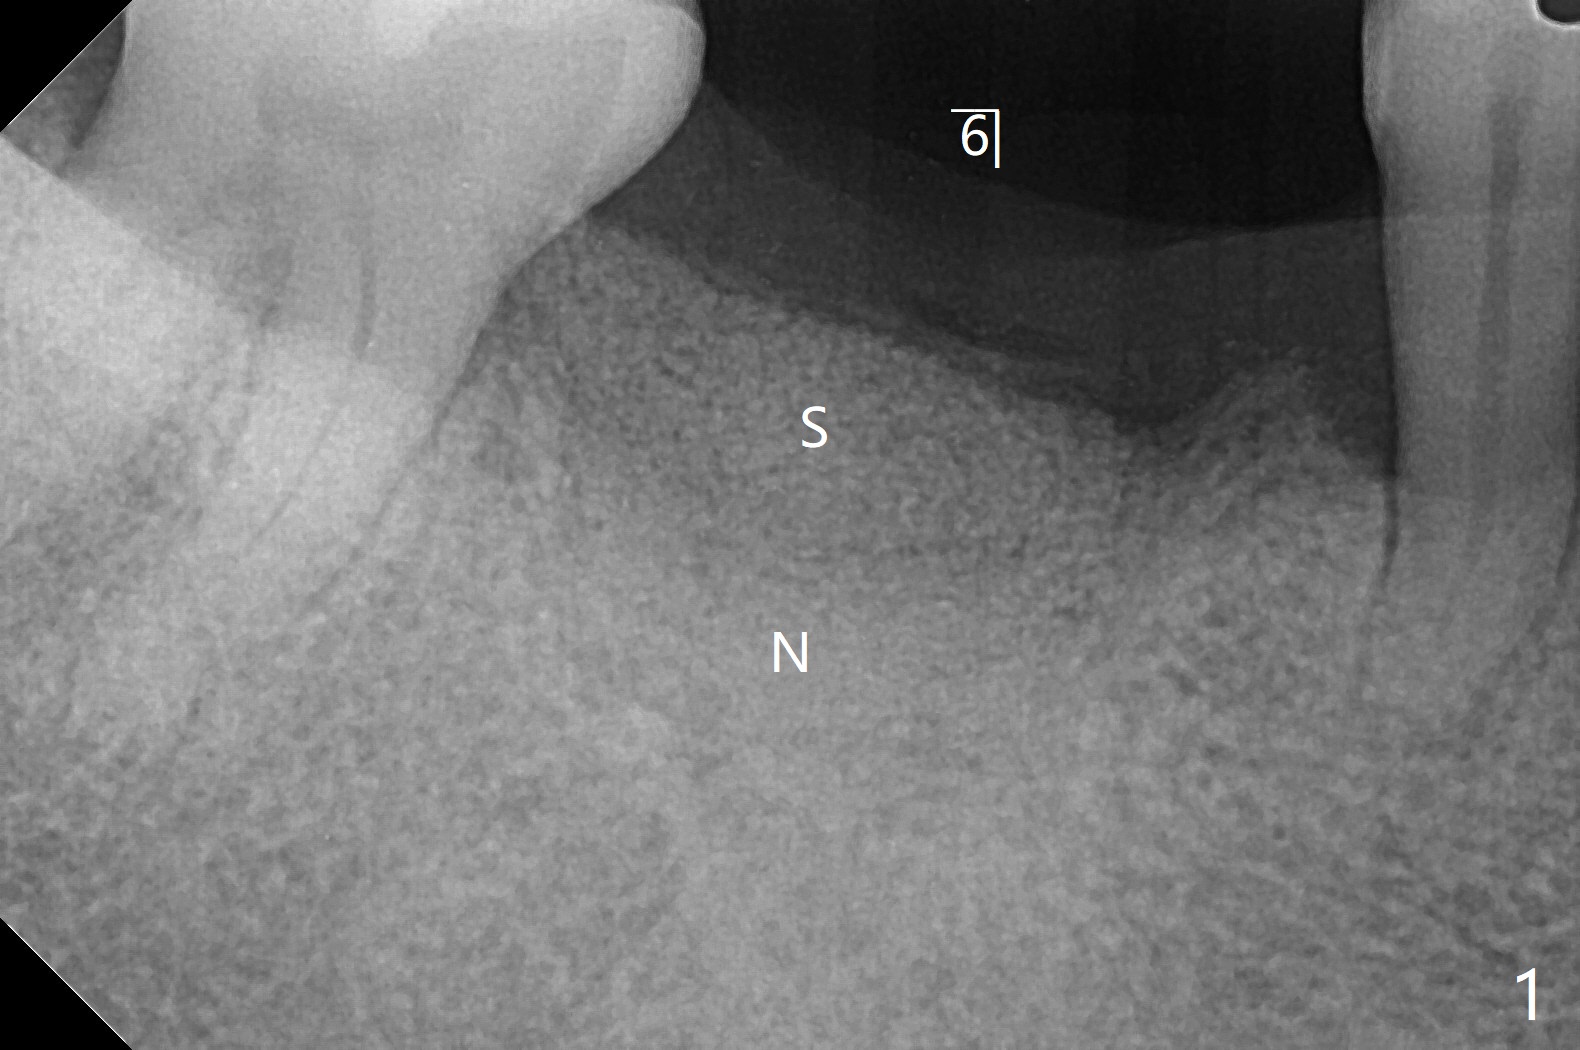

即刻植牙对害怕病人有一个好处,快速结束治疗,安慰病人可是一个麻烦事。即刻种植也可以发生于拔除失败植体之后。今天拔除的失败植牙不知厂家,基台螺丝刀对不上号,所以当植体取出时,病人和我都筋疲力尽,临时决定不做即刻种植。但是出现一个问题,事先准备粘性骨块不够,形成粘性骨块后的上清液不再形成粘性骨块,虽然仍然含有血小板,这样松散的骨粉如果放在牙槽窝上端比较容易丢失。我们解决方法是先把不粘稠的骨粉放在底层(图一:N),把粘性骨块放在上面(S),之后放置PRF膜以及不可吸收膜,使用PTFE缝线和牙周敷料。术后疼痛严重,创伤大。术后4个月牙槽嵴中央塌陷(图二)。不过还能植入5x10毫米植体(图三,四)。Return to Armaments No Deviation Xin Wei, DDS, PhD, MS 1st edition 09/15/2020, last revision 04/06/2021